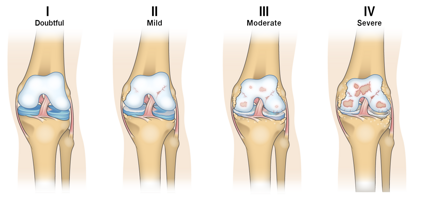

Diagnosi

La diagnosi di artrosi si basa su visita specialistica ortopedica, valutazione clinica, radiografie e talvolta risonanza magnetica.

Ogni paziente presenta un quadro differente: per questo il trattamento deve essere personalizzato, integrando terapia fisica, farmacologica e, quando necessario, chirurgica.

Il trattamento dipende dallo stadio della malattia: esercizi mirati, fisioterapia, infiltrazioni ecoguidate con acido ialuronico o PRP, fino alla sostituzione protesica nei casi più gravi.

Quando la terapia conservativa non è più sufficiente e il dolore limita le attività quotidiane, si può considerare un trattamento chirurgico.